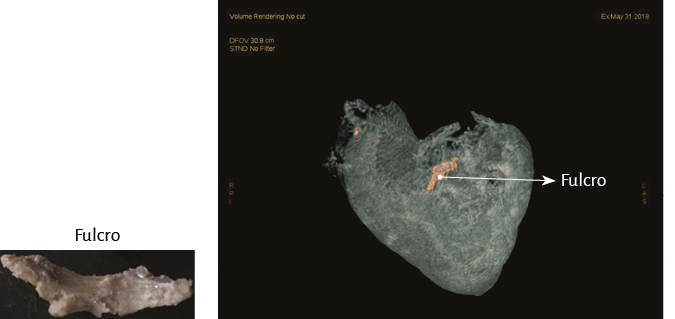

La hélice miocárdica describe dos vueltas en espiral con inserción de sus extremos inicial y terminal en un núcleo cuya estructura es ósea, condroide o tendinosa, de acuerdo con los diferentes especímenes animales y humanos estudiados en nuestras investigaciones. Lo hemos denominado fulcro cardíaco (figuras 17 y 18) (216). Esta inserción es el único sitio perceptible de donde se originan y terminan las fibras miocárdicas. Luego, en esta misma Proposición, se detallará en extensión y profundidad adecuadas este importante tema.

Al inicio del desplegamiento miocárdico lo primero que se interrumpe es un núcleo condroide, donde confluyen ambos extremos del miocardio y al cual hemos denominado fulcro cardíaco (211). Discontinuado este punto, se divorcian los extremos del miocardio. El segmento derecho (inicio) se amarra fundamentalmente a la superficie anterior del fulcro. El segmento ascendente, extremo final del miocardio, ingresa al fulcro fundamentalmente por la parte inferior (figuras 18, 21, 33 y 51). En esta maniobra el miocardio pierde la integridad. Desaparece su solidez integral. El sector del segmento derecho que se extiende desde el fulcro hasta la arteria pulmonar es el tronco pulmotricuspídeo simplemente adosado al segmento ascendente ubicado posteriormente (figuras 29 y 30).

Análisis histológico del fulcro cardíaco. En las investigaciones anatómicas hemos hallado en todos los corazones de bóvidos y de humanos un núcleo cuya estructura histológica es diferente de acuerdo con los especímenes analizados, presentándose como de carácter óseo, condroide o tendinoso. En esta estructura se amarran tanto las fibras musculares del segmento derecho (inserción inicial) como las del segmento ascendente (inserción final). Durante la disección del miocardio, el hallazgo en esta investigación del fulcro cardíaco como núcleo donde se inserta el miocardio nos condujo a otras indagaciones: ¿cuáles eran sus características?, ¿qué ubicación ostenta?, ¿cuál es la histología?, ¿es análoga su presencia en distintas especies?, ¿cómo se inserta el músculo miocárdico en dicha estructura que hemos denominado fulcro cardíaco?

Figura 31. Se demuestra la ubicación del fulcro cardíaco.

Este sitio de inserción que hemos denominado fulcro cardíaco se encuentra en las proximidades de la válvula tricúspide (derecha), de la aorta (superior) y del cordón pulmotricuspídeo (anterior) (figuras 30 y 31). Para poder hallarlo es necesario desplazar hacia la izquierda del observador la arteria pulmonar y el segmento derecho, desnudando la raíz de la aorta. Este gesto descubre al fulcro por debajo de la aorta e inferior al trígono derecho, sin ninguna continuidad con este, por debajo del nacimiento de la arteria coronaria derecha, desprendido de la continuidad aórtica y ubicado como un elemento complementario entre aorta y miocardio (figura 21).

Figura 33. Fulcro cardíaco por debajo de la aorta (corazón bovino). En el ángulo se observa la pieza resecada.

La existencia de una formación ósea, denominada os cordis, en bóvidos y ovejas es un hecho mencionado en ciencia veterinaria. Con posterioridad a nuestra primera publicación en 2018 sobre su hallazgo en el hombre (205), últimamente también fue ubicado en el chimpancé (109). En estas referencias es situada en el mismo sitio en el que nosotros hemos investigado esta estructura, tanto en bóvidos como humanos. Más allá de su mera alusión, hasta nuestras investigaciones nunca se le asignó ninguna función ni el sentido de su presencia, como asimismo careció de descripción en el ser humano (figuras 32 y 33) (216).

En bóvidos, la consistencia del fulcro cardíaco, óseo a la palpación (figuras 34 y 35), ha sido confirmada por la histología (figuras 36 a 38). Su tamaño, corroborado por disección (figura 39) y tomografía computada (figuras 58 y 59), es de aproximadamente 37 a 45 × 15 mm y de forma triangular. El análisis microscópico del fulcro cardíaco bovino muestra una matriz osteocondral trabecular con líneas segmentarias. Su estructura general asemeja al crecimiento metafisario de los huesos largos. A mayor aumento se pueden observar trabéculas óseas con osteoblastos y líneas segmentarias secundarias a aposición ósea. Los mismos hallazgos histológicos se han encontrado en chimpancés (109). La inserción secuencial de las fibras miocárdicas en el fulcro bovino se puede observar en las figuras 40-42.

Imágenes del fulcro cardíaco. Los corazones de bovino, estudiados con tomografía computada (figuras 58-60), resonancia magnética (figuras 61 y 62) y radiología simple (figura 63) evidenciaron el núcleo osteo-condroide hallado en la disección, observándose la misma morfología y tamaño análogo. En la tomografía humana hemos encontrado, en el análisis de la región donde se encuentra el fulcro cardíaco a través de las disecciones realizadas, la presencia de una intensidad en unidades Hounsfield por encima de 110 UH, mientras que el músculo adyacente tiene unidades por debajo de 80 UH. De esta manera, en la imagen, la estructura del fulcro alcanza un promedio de 132 ± 4,5 HU. En las áreas adyacentes, correspondiente al músculo miocárdico, este valor se ubicó entre 47,96 ± 12,5 y 77,59 ± 21,64 HU (figura 64).

Nuestras investigaciones han demostrado, en el trayecto del segmento septal del anillo aórtico que se extiende desde el trígono izquierdo al derecho, la presencia de un núcleo sólido que hemos denominado fulcro cardíaco (por debajo del origen de la arteria coronaria derecha), donde se amarra el miocardio continuo en su inicio y al final, que como todo músculo necesita un apoyo para cumplir con su función.